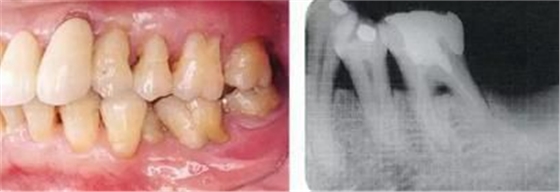

▲圖5-1,2

▲圖5-1 左下5舌側(cè)移位,頰系帶高位附著,附著齦不足,口腔前庭狹小,左下6根分叉病變,左下7擴(kuò)散性骨組織吸收深達(dá)根尖部等,存在非常多的問(wèn)題。

▲圖5-2 確認(rèn)左下7骨組織吸收深達(dá)根尖部,初期治療時(shí)拔除。將左下7拔除后的X光片。